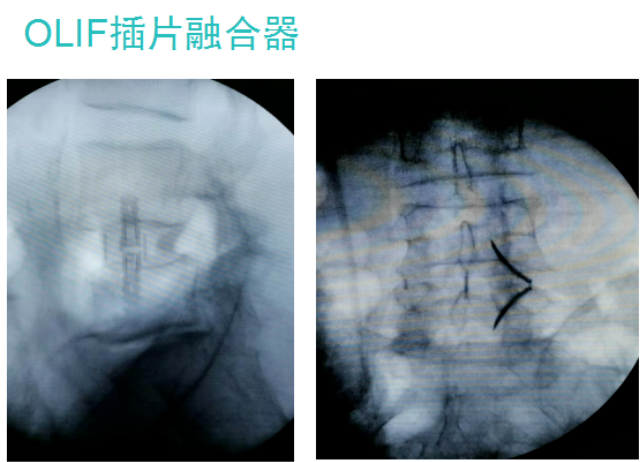

2021年7月2日-4日,中国医师协会第三届显微外科医师年会在宁波举行。我院医疗院长桃春辉当选本届全国委员,会上代表医院报告我院开展的显微镜下脊柱微创OLIF技术,受到了与会专家们关注。

“OLIF作为一种更加微创的椎间融合术,近几年在国内各大医院逐渐开展,获得越来越多临床医生的认可”桃春辉院长介绍,该手术经左下腹腹外斜肌、腹内斜肌、腹横肌的肌间隙进入腹膜外间隙,在左侧腰大肌和腹主动脉之间安放工作通道,可通过大血管间隙及腰大肌间入路进行手术,可明显减少手术创伤、缩短手术时间、减少术中出血、缩短住院时间及患者康复时间。